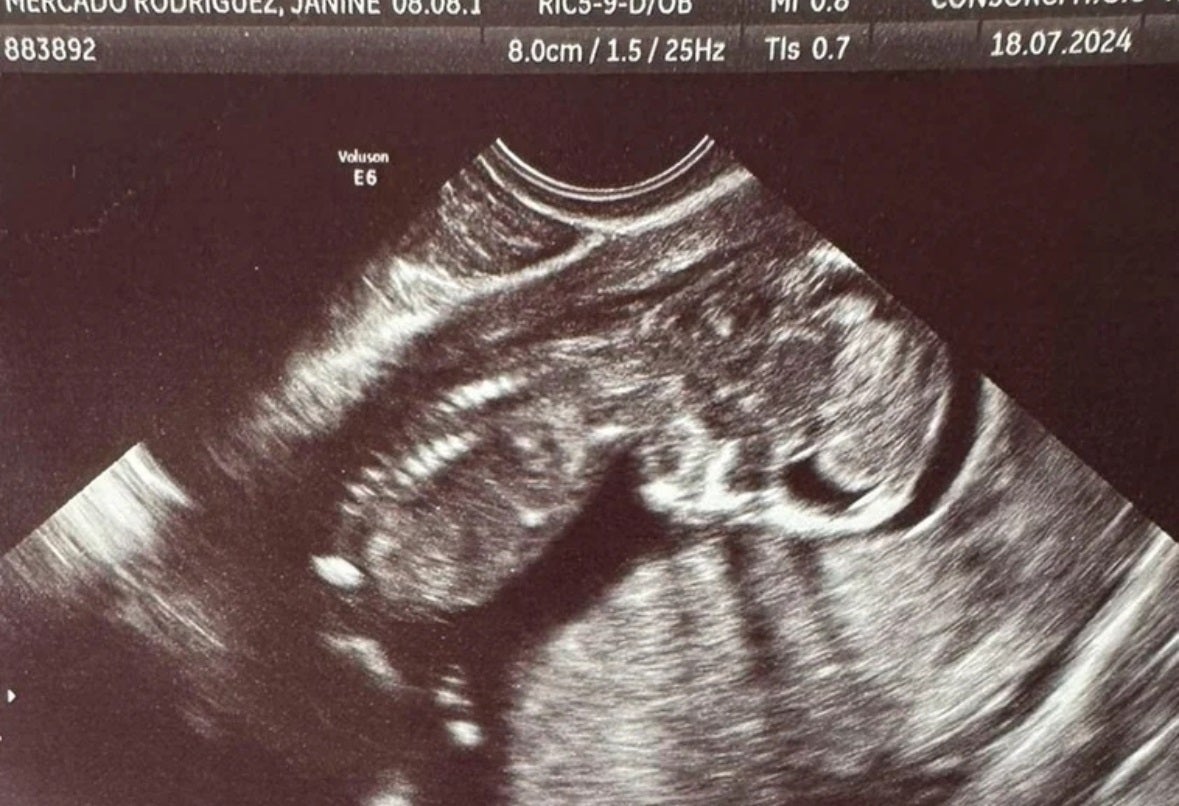

Ecografía de la pequeña Escarlett facilitada por su abuela. LP

Puede que solo un trámite procesal más, después de que la magistrada reconociera que sí, que la niña que llevaba en su vientre una mujer embarazada cuando la barrancada, debía ser considerada una víctima. La número 229. Demasiadas. El caso es que Escarlett, como así debía haberse llamado la pequeña, está más cerca de ser persona.

«Janine iba a ser madre soltera. Su primera hija era su ilusión y trabajaba duro por ella al volante de un camión. Ahora he perdido a las dos y sólo pido justicia». Lo decía la madre de Janine Mercado Rodríguez. La mamá de Escarlett, arrastrada por las aguas aquel terrible 29 de octubre.